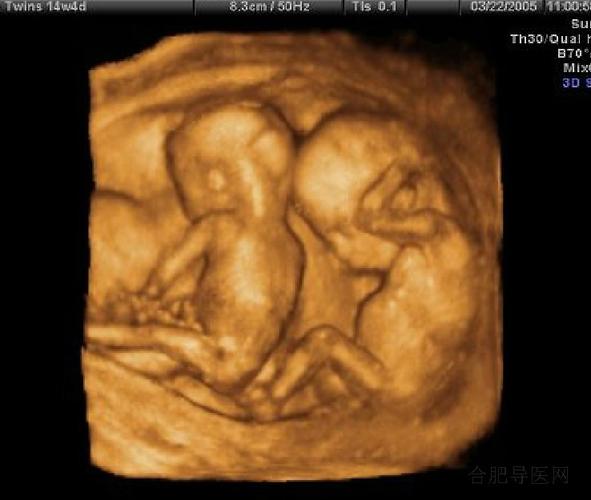

b超四维,四维b超

孕妈做四维时医生常说的这几句暗语男宝女宝你都听懂了么

四维彩超的最佳时间,很多孕妈都做早了

四维超声

四维彩超

胎儿四维照片

四维图片胎儿全图